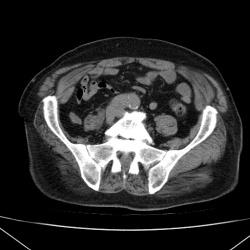

Что за образования в брюшной полости вдоль левой поясничной мышцы? Лимфоузлы?